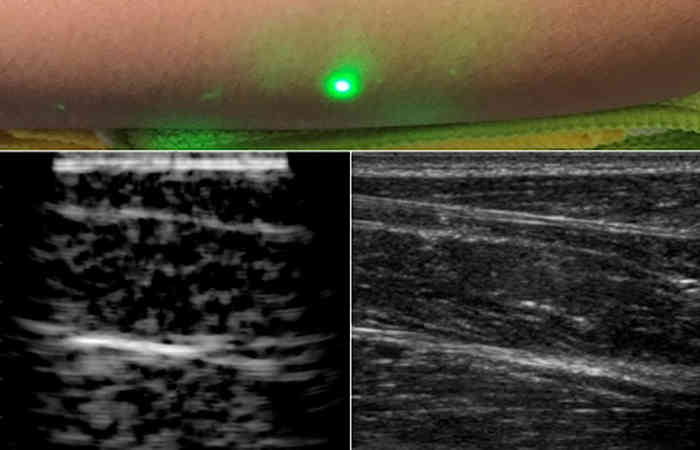

शोधकर्ताओं ने कई स्वयंसेवकों की कलाई को स्कैन किया। एक समान विशेषता मांसपेशियों, वसा और हड्डियों के ऊतकों में देखी गई, जो त्वचा से लगभग छह सेमी नीचे थी। आधा मीटर की दूरी पर, स्वयंसेवकों की छवियों को एक लेजर का उपयोग करके लिया गया था, और सभी एक पारंपरिक अल्ट्रासाउंड के समान थे।

अध्ययन के दौरान, शोधकर्ताओं ने एक विशेष तरंग दैर्ध्य में एक लेजर के साथ त्वचा में प्रकाश संचारित किया और इसे रक्त वाहिकाओं में अवशोषित कर लिया। लेजर की गर्मी के कारण, रक्त वाहिकाएं तेजी से फैलती हैं और शांत होने के बाद अपने मूल आकार में लौट आती हैं। यह तब तक जारी रहता है जब तक कि लेजर की दूसरी तरंग दैर्ध्य इसमें प्रवेश नहीं करती है।

यह यांत्रिक तरंगों द्वारा ध्वनि तरंगों को उत्पन्न करता है। ध्वनि तरंगें ऊपर की ओर उठती हैं और त्वचा से जुड़ा सिग्नल डिटेक्टर इसे पहचानने योग्य छवि में ढाल देता है। हालांकि, ध्वनि तरंगों की पहचान करने के लिए डिटेक्टर को शरीर के सीधे संपर्क में रखना आवश्यक है।